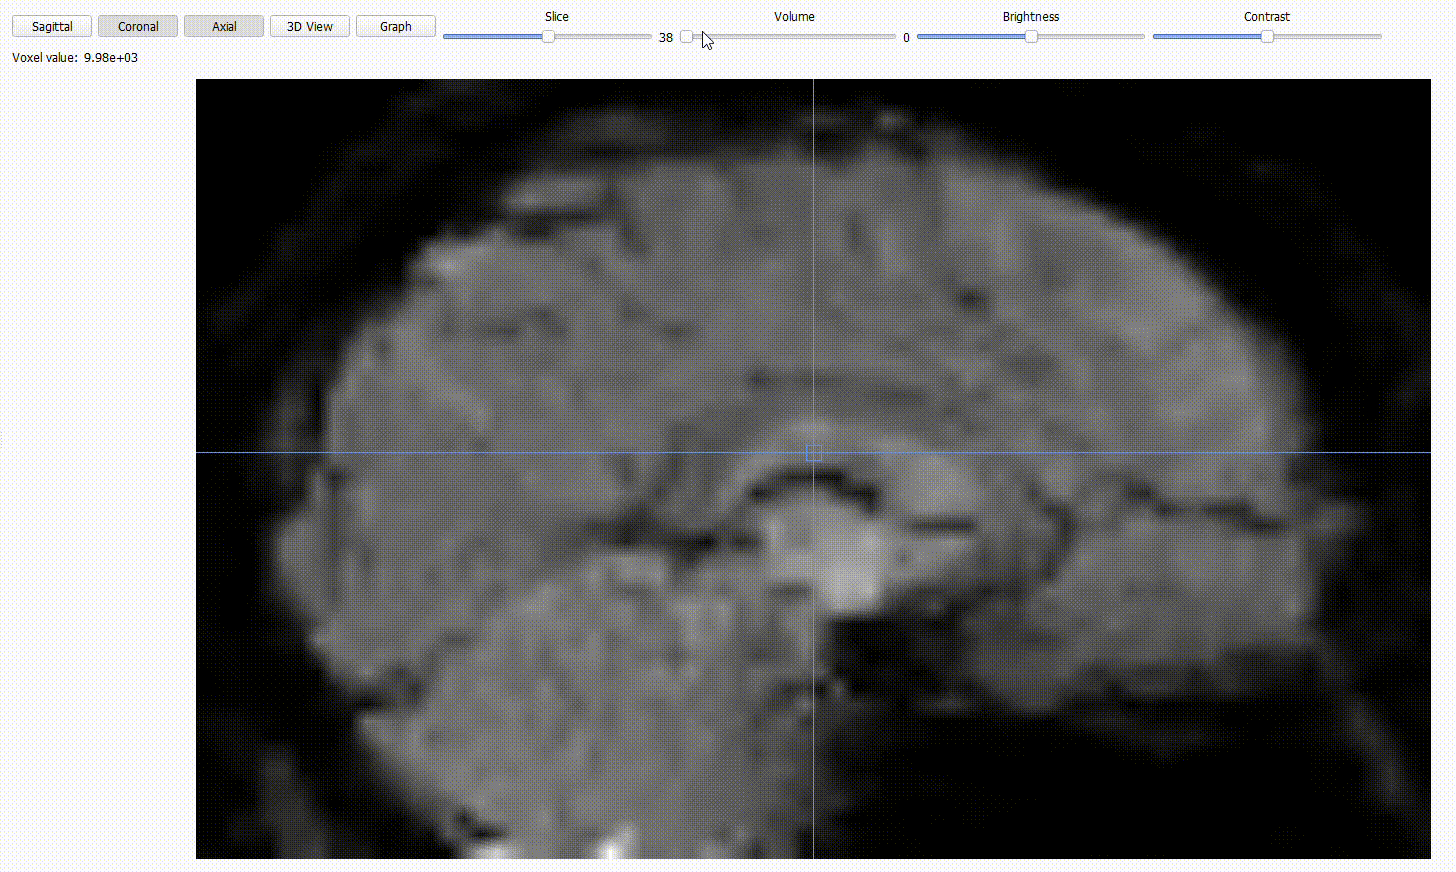

Sequence type view: BIDSplorer can open NIfTI images (.nii/.nii.gz) across different sequence types (anat, func, fmap, dwi). Use the different option to

Inspect the three orthogonal planes with the

Axial,CoronalandSagittalbuttons.

Scroll through the 2D cross-sections of the current plane with the

Slicestoggle.

Adjust

brightnessandcontrastto improve visibility.

For functional (BOLD) images, you can scroll through time using the

volumetoggle.